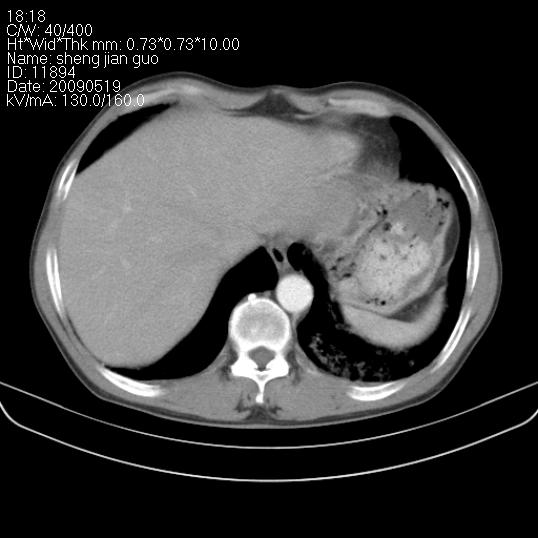

以下是引用zjzjr在2009-5-19 17:25:00的发言:[br]支持楼主考虑,另左肺下叶阻塞性炎症。

以下是引用zhao_bin2008在2009-5-19 17:48:00的发言:[br]支持左肺下叶周围型肺癌并阻塞性肺炎。

以下是引用杀毒软件在2009-5-19 17:36:00的发言:[br]支持楼主

以下是引用zsl6918在2009-5-20 7:10:00的发言:[br]左侧中心型肺癌!